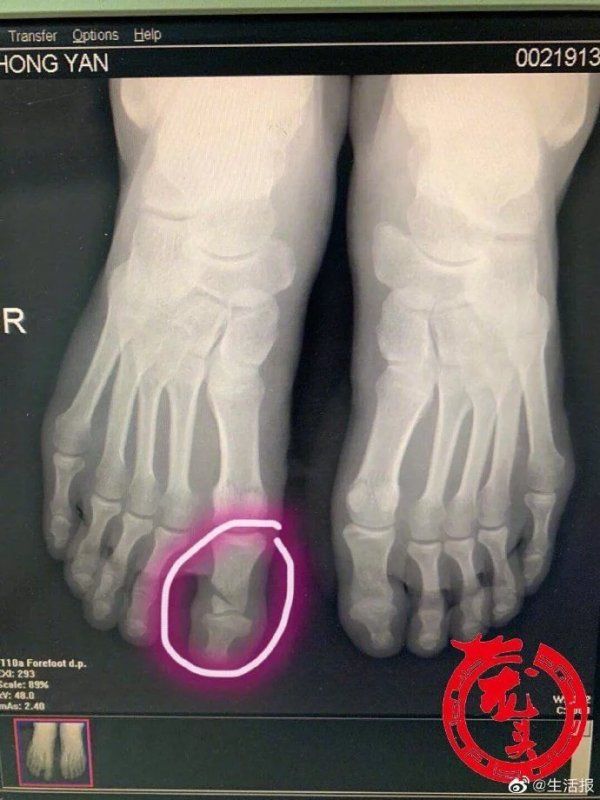

【嫌家中板凳不平 男子拿起电锯,脚下一滑悲剧了】嫌家中板凳不平,男子临时当起了“木匠”,不料脚下一滑,电锯从手中脱落,砸伤两个脚趾,还把其中一个脚趾砸骨折了。近日,哈尔滨市民张先生(化姓)在家中本想勤快一把,没成想突遭意外,后悔不迭。 几天前,张先生发现家中新买的板凳坐着有点不平,找人帮忙有点麻烦,家里正好有电锯,平时没事就爱修修补补的张先生自己当起了临时“木匠”。没想到当天张先生穿的是拖鞋,加上地面上有些潮湿,单腿着地的他一个没站稳,摔倒的时候,手中的电锯正好砸到了右脚上,锋利的刀刃将大拇脚指割伤,顿时血流如注,张先生疼得满头大汗。家人见状,急忙把他送到了哈医大一院急诊科。当时正在缓冲区值班的骨一科副主任耿硕检查发现,患者为电锯开放伤,大拇脚指骨折,血管、肌腱均被割断,紧急做了急诊清创手术。